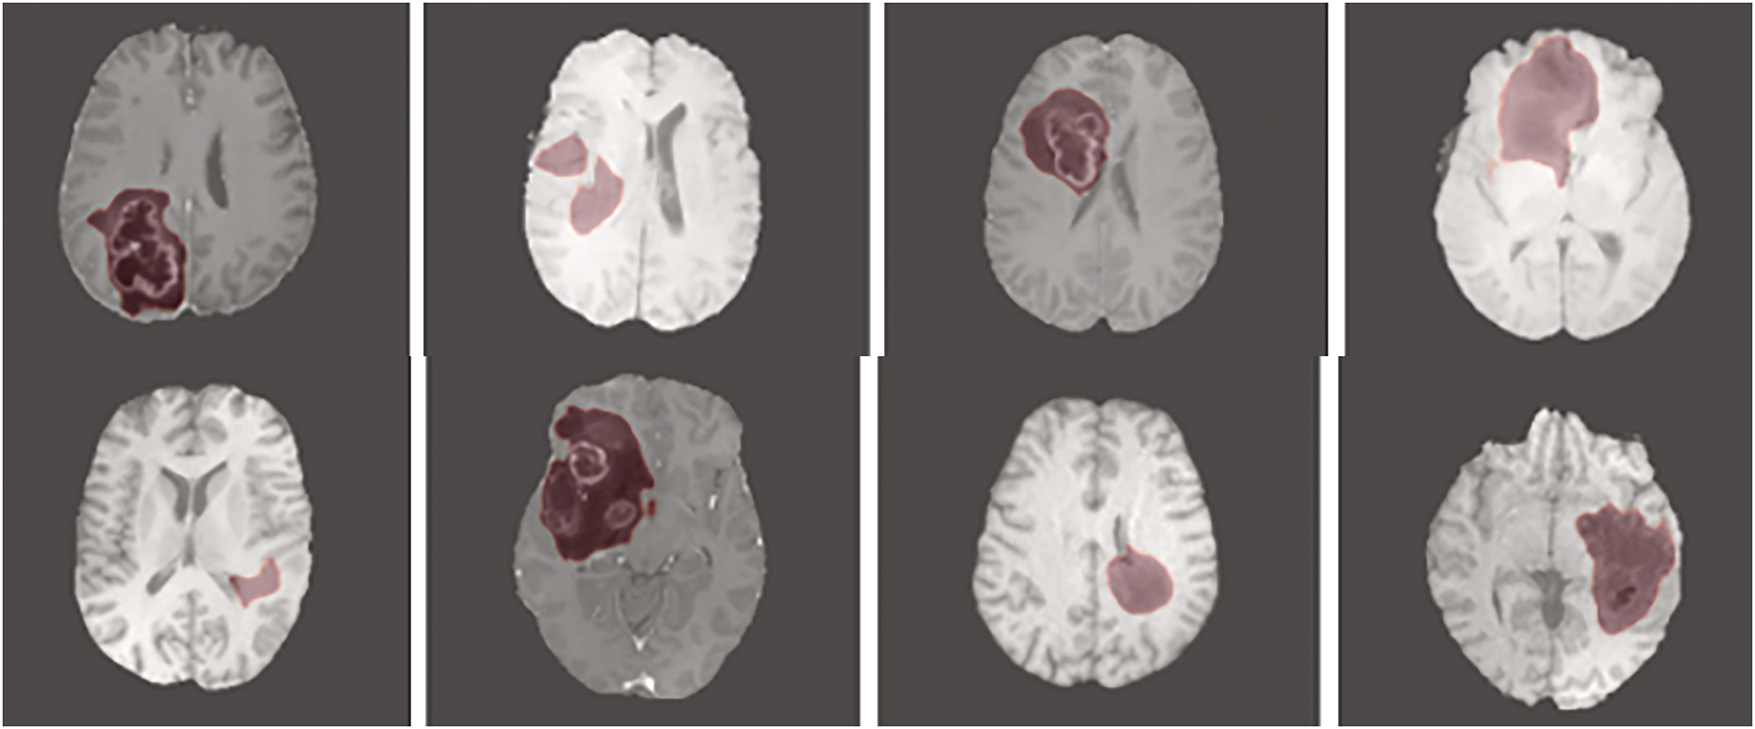

Figure 5: Output image of the proposed model

The proposed segmentation model is executed on Python 3.7 software environment, implemented on a system with 4-TB hard drive, 128-GB random access memory, windows 11 (64-bit) operating system, and Intel i7 12th generation processor. The training of SNFRC is carried out using NVIDIA RTX 2090Ti GPUs, enabling convergence within a reasonable timeframe in accordance with modern deep learning practices in the medical imaging field. Although the computational requirements are higher compared to simpler architectures, this is justified by the improved segmentation performance and enhanced generalizability. Additionally, SNFRC maintains efficient inference speeds, supporting real-time deployment once training is complete. The libraries named TensorFlow, Keras, Numpy, and OpenCV are used to investigate the proposed model’s efficacy. In the acquired datasets, tumor structures are categorized into three sub-regions, namely, Whole-Tumors (WTs) regions, Enhancing Tumors (ETs) regions, and Tumor-Cores (TCs) regions. The ET regions contain label 4, the WT regions exclude ‘edema’ region and comprise the labels 1, 3 and 4, and the TC regions consist of four sub-tumoral classes, such as labels 1, 2, 3, and 4. For each dataset, the training, testing, and validation sets are divided in a 70%, 15%, and 15% ratio, respectively. In this manuscript, the model’s effectiveness is evaluated using the following performance metrics: Hausdorff Distance (HD), recall, F1-measure, Dice Similarity Coefficient (DSC), accuracy, and precision. In brain tumor segmentation (BTS), HD, DSC, Intersection over Union (IoU), and volume similarity are the primary evaluation measures used to validate the efficacy of the segmentation model. The DSC quantifies the overlap between the actual labeled area and the predicted lesion area, and is mathematically defined in Eq. (13). HD is a mathematical metric used to measure the dissimilarity between two sets of points (T and P) in a metric space, as represented in Eq. (14). In segmentation tasks, the correctness of each sample’s identification is related not only to classification but also to localization. Localization accuracy is assessed using IoU, as defined in Eq. (15). Additionally, the overlap among segmented regions is evaluated using volume similarity, expressed in Eq. (16).